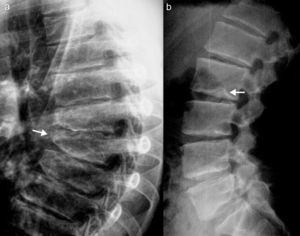

Reporte de casoPaciente varón de 17 años de edad; a los 13 años presentó dolor de cadera derecha y de rodilla izquierda. Cinco meses más tarde presentó inflamación de ambas rodillas y de interfalángicas de la mano derecha. El paciente refirió historia de dificultad al caminar desde los 3 años de edad. El examen físico mostró un adolescente con marcha anormal, escoliosis espinal y cifosis de la columna torácica. La movilidad de la columna lumbar, coxofemorales, rodillas, tobillos e interfalángicas de la mano derecha estaba severamente limitada. Las radiografías de manos y pies (fig. 1a y b), caderas y rodillas (fig. 2a y b) revelaron osteopenia difusa, ensanchamiento tubular de las epífisis y pérdida del espacio articular, sin lesiones erosivas; las radiografías de cadera y rodillas mostraron además cambios degenerativos, con cabezas femorales ensanchadas. Las vértebras torácicas y lumbares, con vértebras aplanadas e irregularidades en las mesetas vertebrales (fig. 3a y b). La proteína C reactiva y la velocidad de sedimentación globular eran normales.

La DPSR simula clínicamente una artritis idiopática juvenil en etapas tempranas1,2; sin embargo, las evidencias que establecen el diagnóstico de esta displasia ósea son la afectación articular no inflamatoria y los hallazgos radiológicos característicos, como la presencia de epífisis ensanchadas, osteoporosis generalizada y platispondilia3.